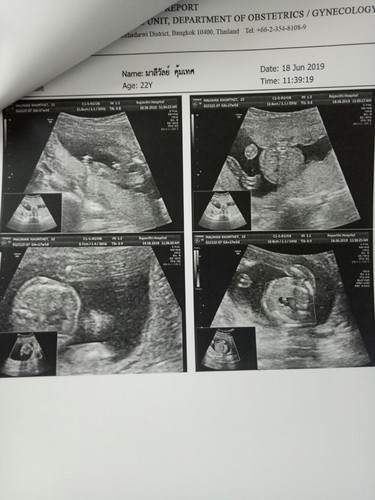

ใบอัลตร้าซาวด์

แม่คนไหนดูเป็นรบกวนดูช่วยหน่อยจ้าว่าเป็นเพศไหน

รูปซ้ายบน หมอถ่ายอวัยวะเพศให้แล้วดูละค่า